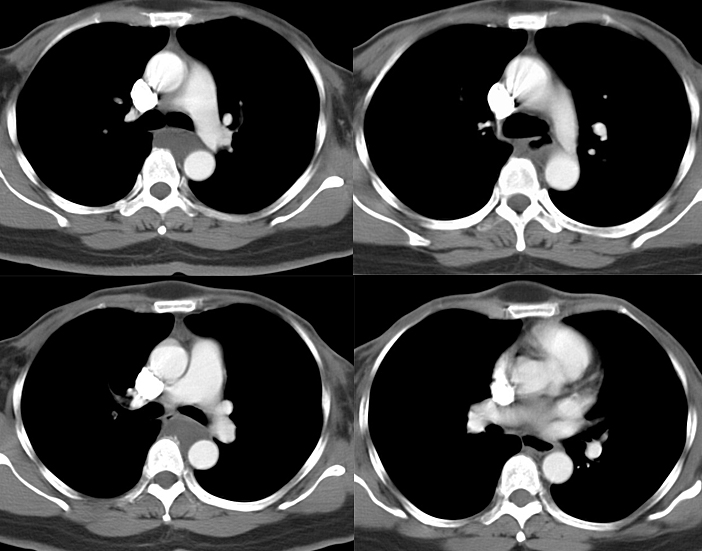

Bronch Cyst 2 CT